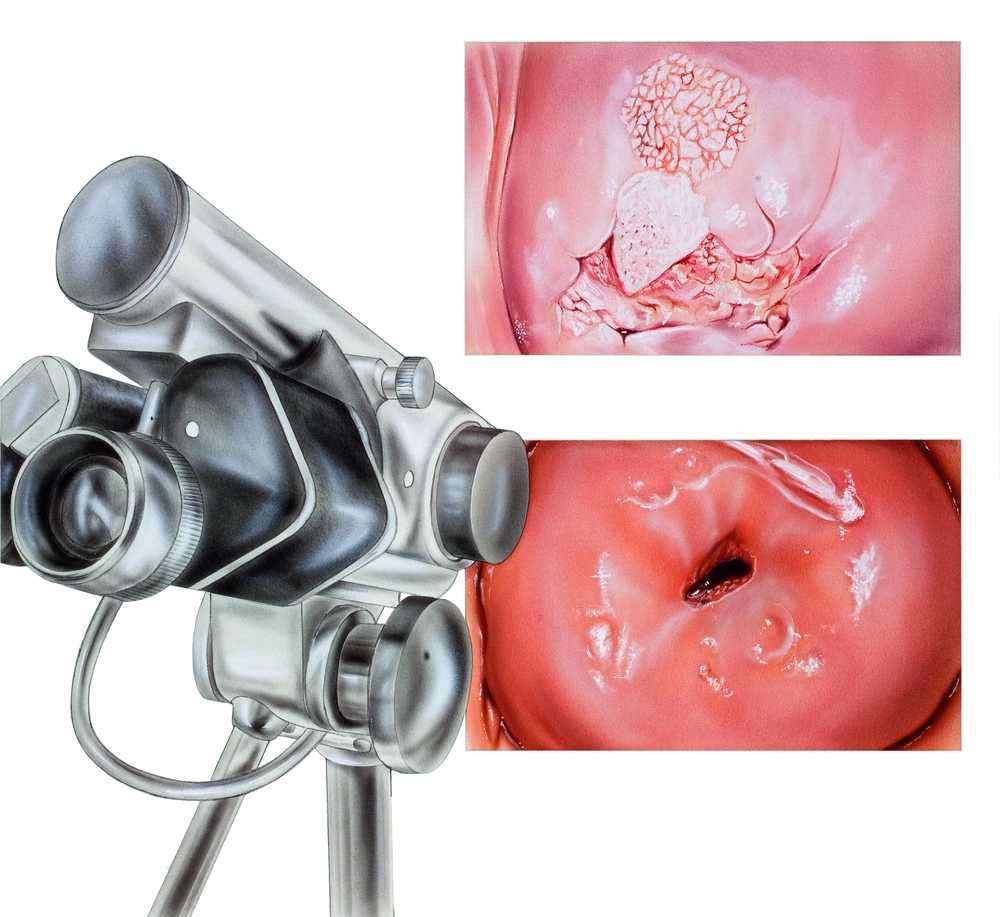

Что такое кондиломы?

Кондиломы - это одно из самых распространенных заболеваний, передающихся половым путем. Они вызваны вирусом папилломы человека (ВПЧ) и могут появляться на внешних половых органах, анусе, ротовой полости и других областях тела.

Симптомы кондилом могут варьироваться, и визуальное представление этого заболевания может быть различным. Некоторые кондиломы выглядят как небольшие бугорки или бородавки, в то время как другие могут иметь форму плоских пятен или цветных наростов.